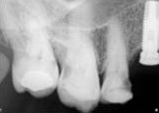

antes depois